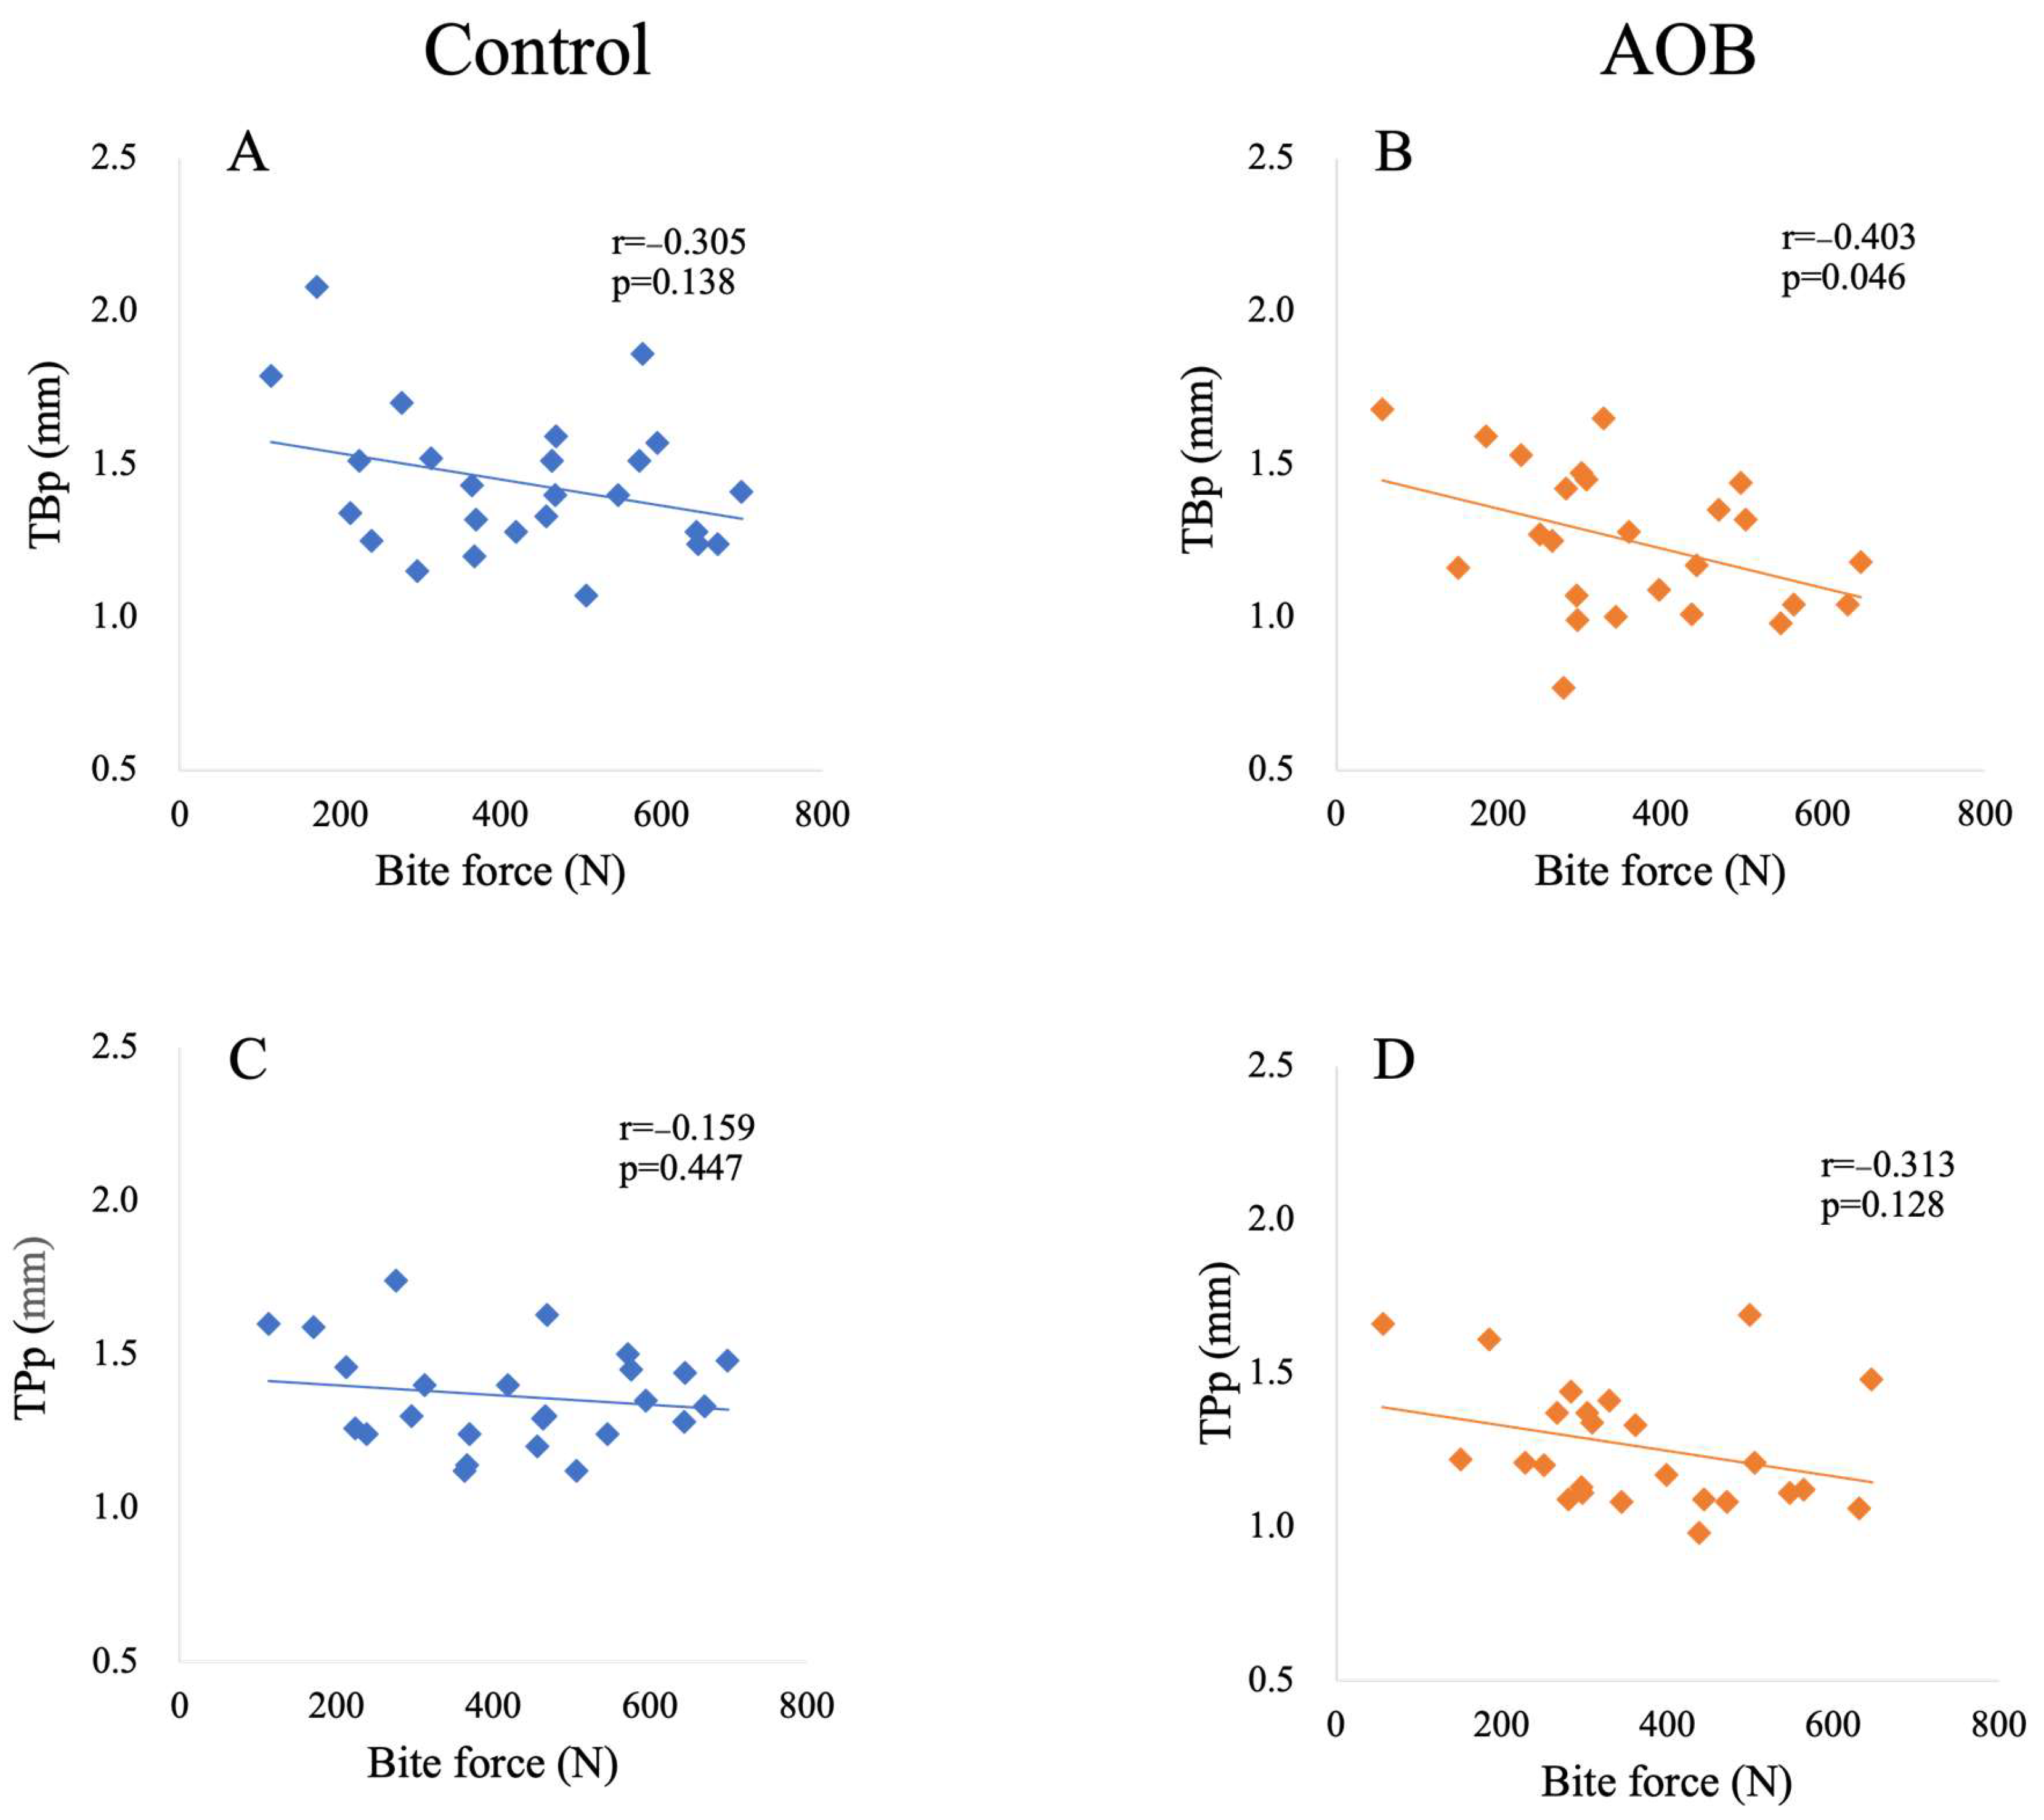

3. Results

| TBp vs. bite force | −0.305 (0.138) | −0.403 (0.046 *) |

| TPp vs. bite force | −0.159 (0.447) | −0.313 (0.128) |